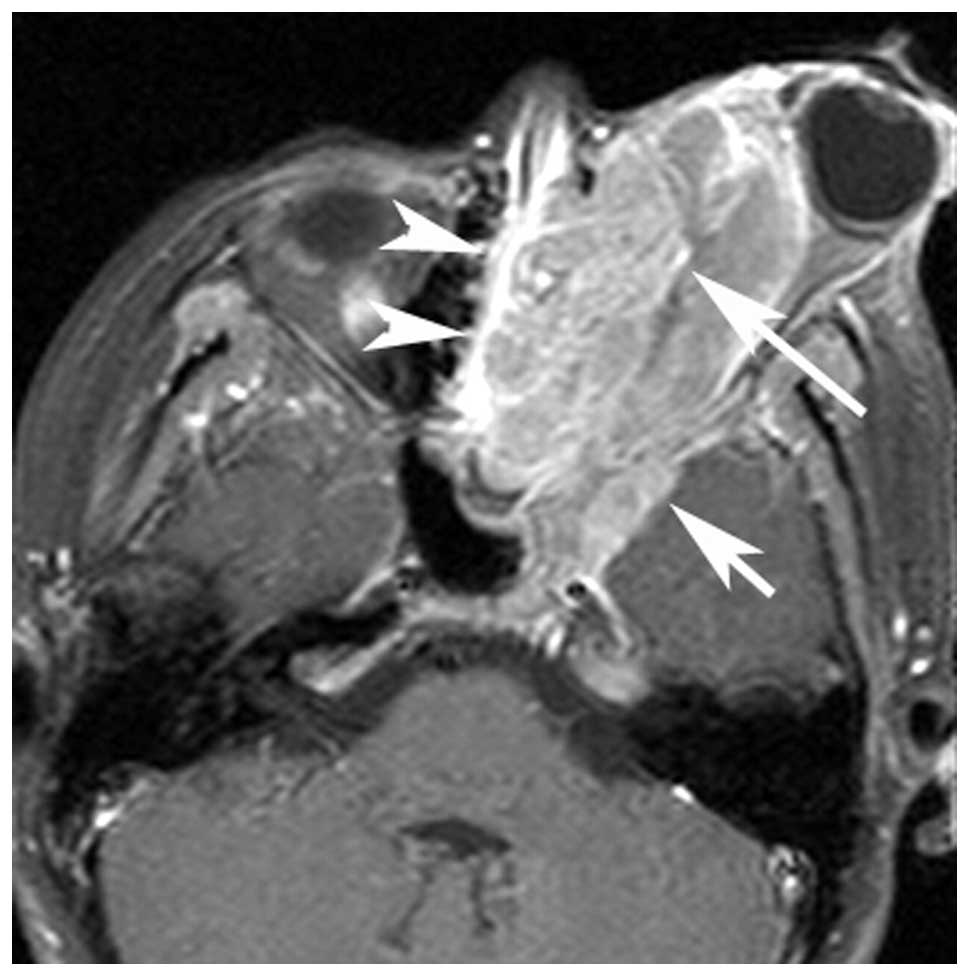

Orbital Rhabdomyosarcoma | Image | Radiopaedia.org

radiopaedia.org

radiopaedia.org

Orbital Rhabdomyosarcoma

www.medscape.com

www.medscape.com

rhabdomyosarcoma orbital

Orbital Rhabdomyosarcoma - Page 2

www.medscape.com

www.medscape.com

rhabdomyosarcoma orbital figure

Neuropathology Blog: Orbital Rhabdomyosarcoma

neuropathologyblog.blogspot.com

neuropathologyblog.blogspot.com

rhabdomyosarcoma orbital neuropathology sikandar bushra pathology twitter reply

Rhabdomyosarcoma (orbit) | Radiology Reference Article | Radiopaedia.org

radiopaedia.org

radiopaedia.org

rhabdomyosarcoma orbit radiology radiopaedia

Rhabdomyosarcoma (orbit) | Radiology Reference Article | Radiopaedia.org

radiopaedia.org

radiopaedia.org

rhabdomyosarcoma orbit orbital hemangioma radiopaedia radiology imaging

Rhabdomyosarcoma Of Orbit | American Journal Of Neuroradiology

www.ajnr.org

www.ajnr.org